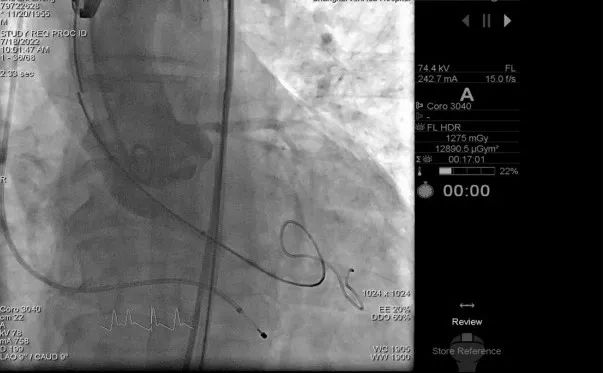

4、食道超声及根部造影结果显示无瓣周漏,跨瓣压差仅为4mmHG,左右冠脉均有显影,冠脉血流未受影响;